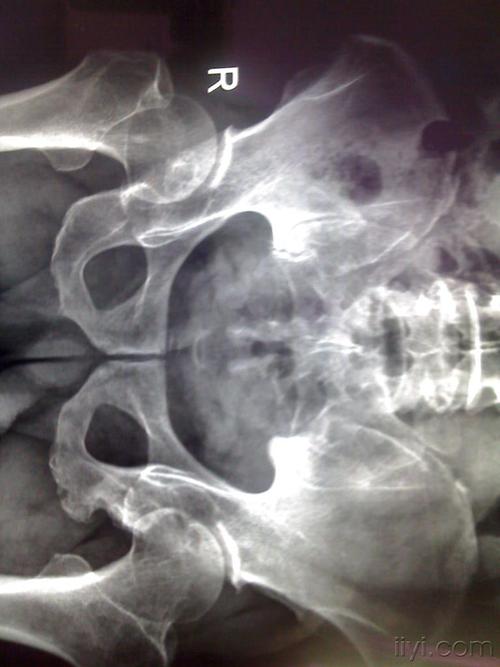

左侧坐骨支骨折图片

左侧坐骨支骨折图片,坐骨支骨图片

2013-12-07 陶威宇 医师 8月1号去医院复查了,左侧坐骨及耻骨骨质形态